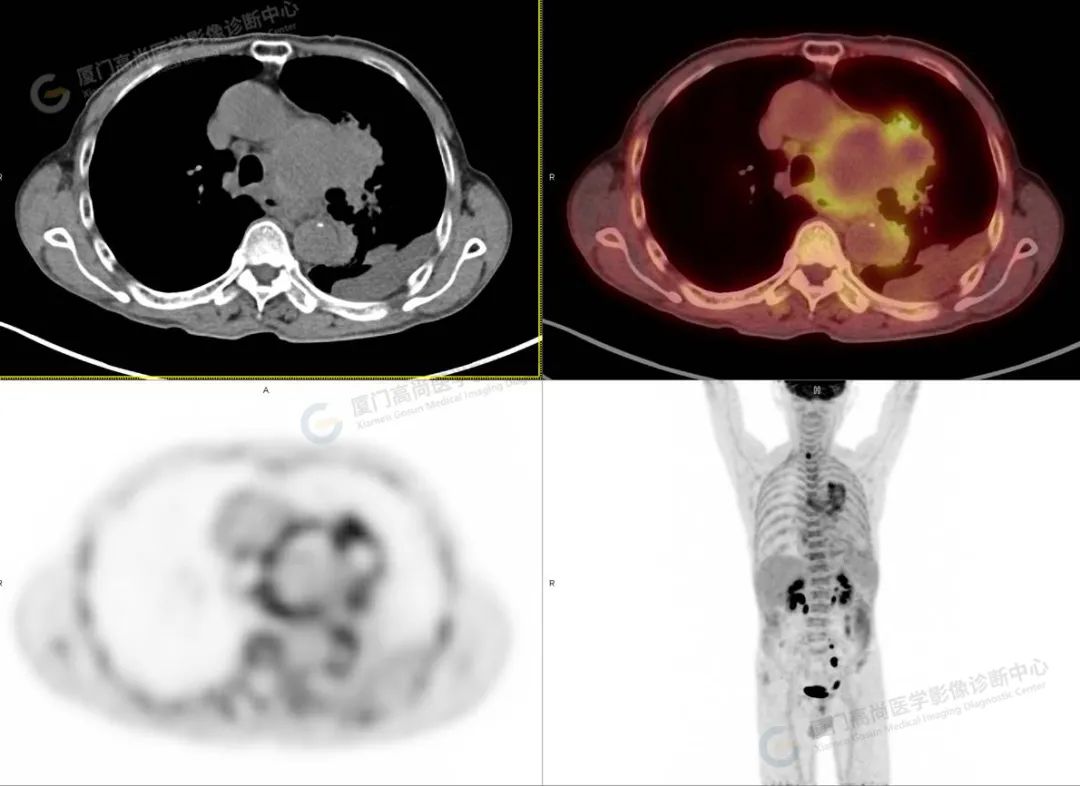

影像诊断:主动脉弓部瘤样扩张,并钙化斑内移,中心部位代谢减低,周围部分代谢增高,考虑主动脉夹层或动脉瘤破裂可能,并左侧胸腔积血、积液,动脉硬化,请结合临床及主动脉 CTA 进一步检查明确。

本中心发现王先生属于主动脉夹层或者主动脉瘤破裂可能,属心血管疾病的灾难性危急重症,如不及时诊治,48 小时内死亡率可高达 50%,故立即与其主管医师联系,并录制图像视频传达至医师,建议行主动脉 CTA 检查明确。后紧急行胸腹主动脉 CTA 示:主动脉弓假性动脉瘤形成伴边缘机化性血肿,并左侧胸腔包裹性积液、积血。